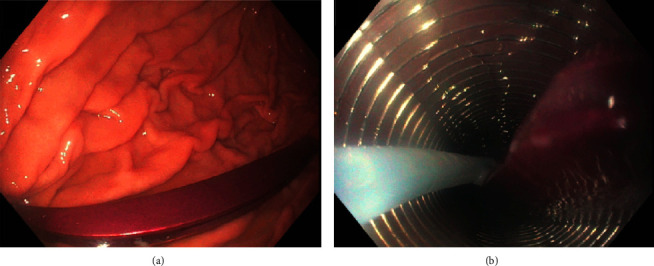

导言:异物(FB)摄入是临床实践中经常遇到的情况。大多数误食的异物通常会自行排出,无需干预。内窥镜取出异物是创伤最小的方法,只有极少的 1%需要手术干预。病例介绍。我们介绍了一例 30 岁男性的病例,他摄入了位于胃部和小肠的多个 FB。虽然通过内窥镜成功切除了胃中的 FB,但由于穿孔问题和专业知识有限,切除小肠中的第二个 FB 证明具有挑战性。考虑到患者之前曾因手术治疗导致大切口疝,医生不建议进行手术切除。因此,在外科医生和介入放射科医生(IR)的共同决定下,在 IR 技术的帮助下采用了透视引导下的切除方法:本病例凸显了在内窥镜和外科手术均不可行的情况下,采用创伤较小的替代方法的可能性。

Introduction: Foreign body (FB) ingestion represents a frequently encountered scenario in clinical practice. Most ingested FBs typically pass spontaneously, requiring no intervention. Endoscopic removal stands out as the least invasive method, with only a minimal 1% needing surgical intervention. Case Presentation. We present a case of a 30-year-old male who ingested multiple FBs located in the stomach and small bowel. While successful removal of the stomach FB was achieved through endoscopy, the second FB in the small bowel proved challenging due to perforation concerns and limited expertise. Given a history of prior surgical intervention resulting in a large incisional hernia, surgical removal was discouraged. Consequently, a collaborative decision involving surgeon and interventional radiologist (IR) led to the adoption of a fluoroscopic-guided removal approach facilitated by IR techniques.